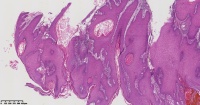

角化棘皮瘤?

性别

男

年龄

45岁

临床诊断

一般病史

面部包块

标本名称

大体所见

图2

倾向脂溢性角化病。